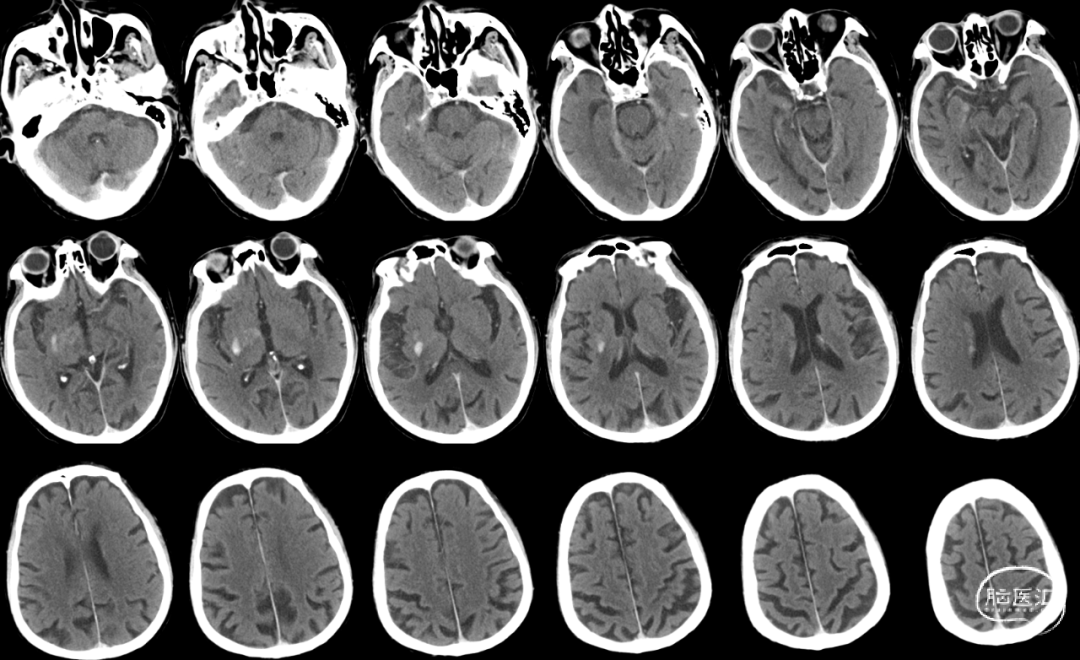

颅脑CT:未见出血,ASPECTS评分 9分。

颅脑CT ASPECTS 9分。

Cranial DWI:右侧壳核、侧脑室旁小片状+皮层点状弥散受限。

Cranial SWI:SVS+AHVs RMCA M1长条血栓。

T2 Flair:丰富的高信号血管征(HVS)。

Reexamination Cranial CT:梗死区造影剂渗出。

Reexamination Cranial DWI:无明显的血栓向远端逃逸或小血栓脱落后新形成的皮层或分水岭点片状梗死。

Reexamination Cranial SWI:壳核后部,造影剂渗出最多的地方再灌注损伤。